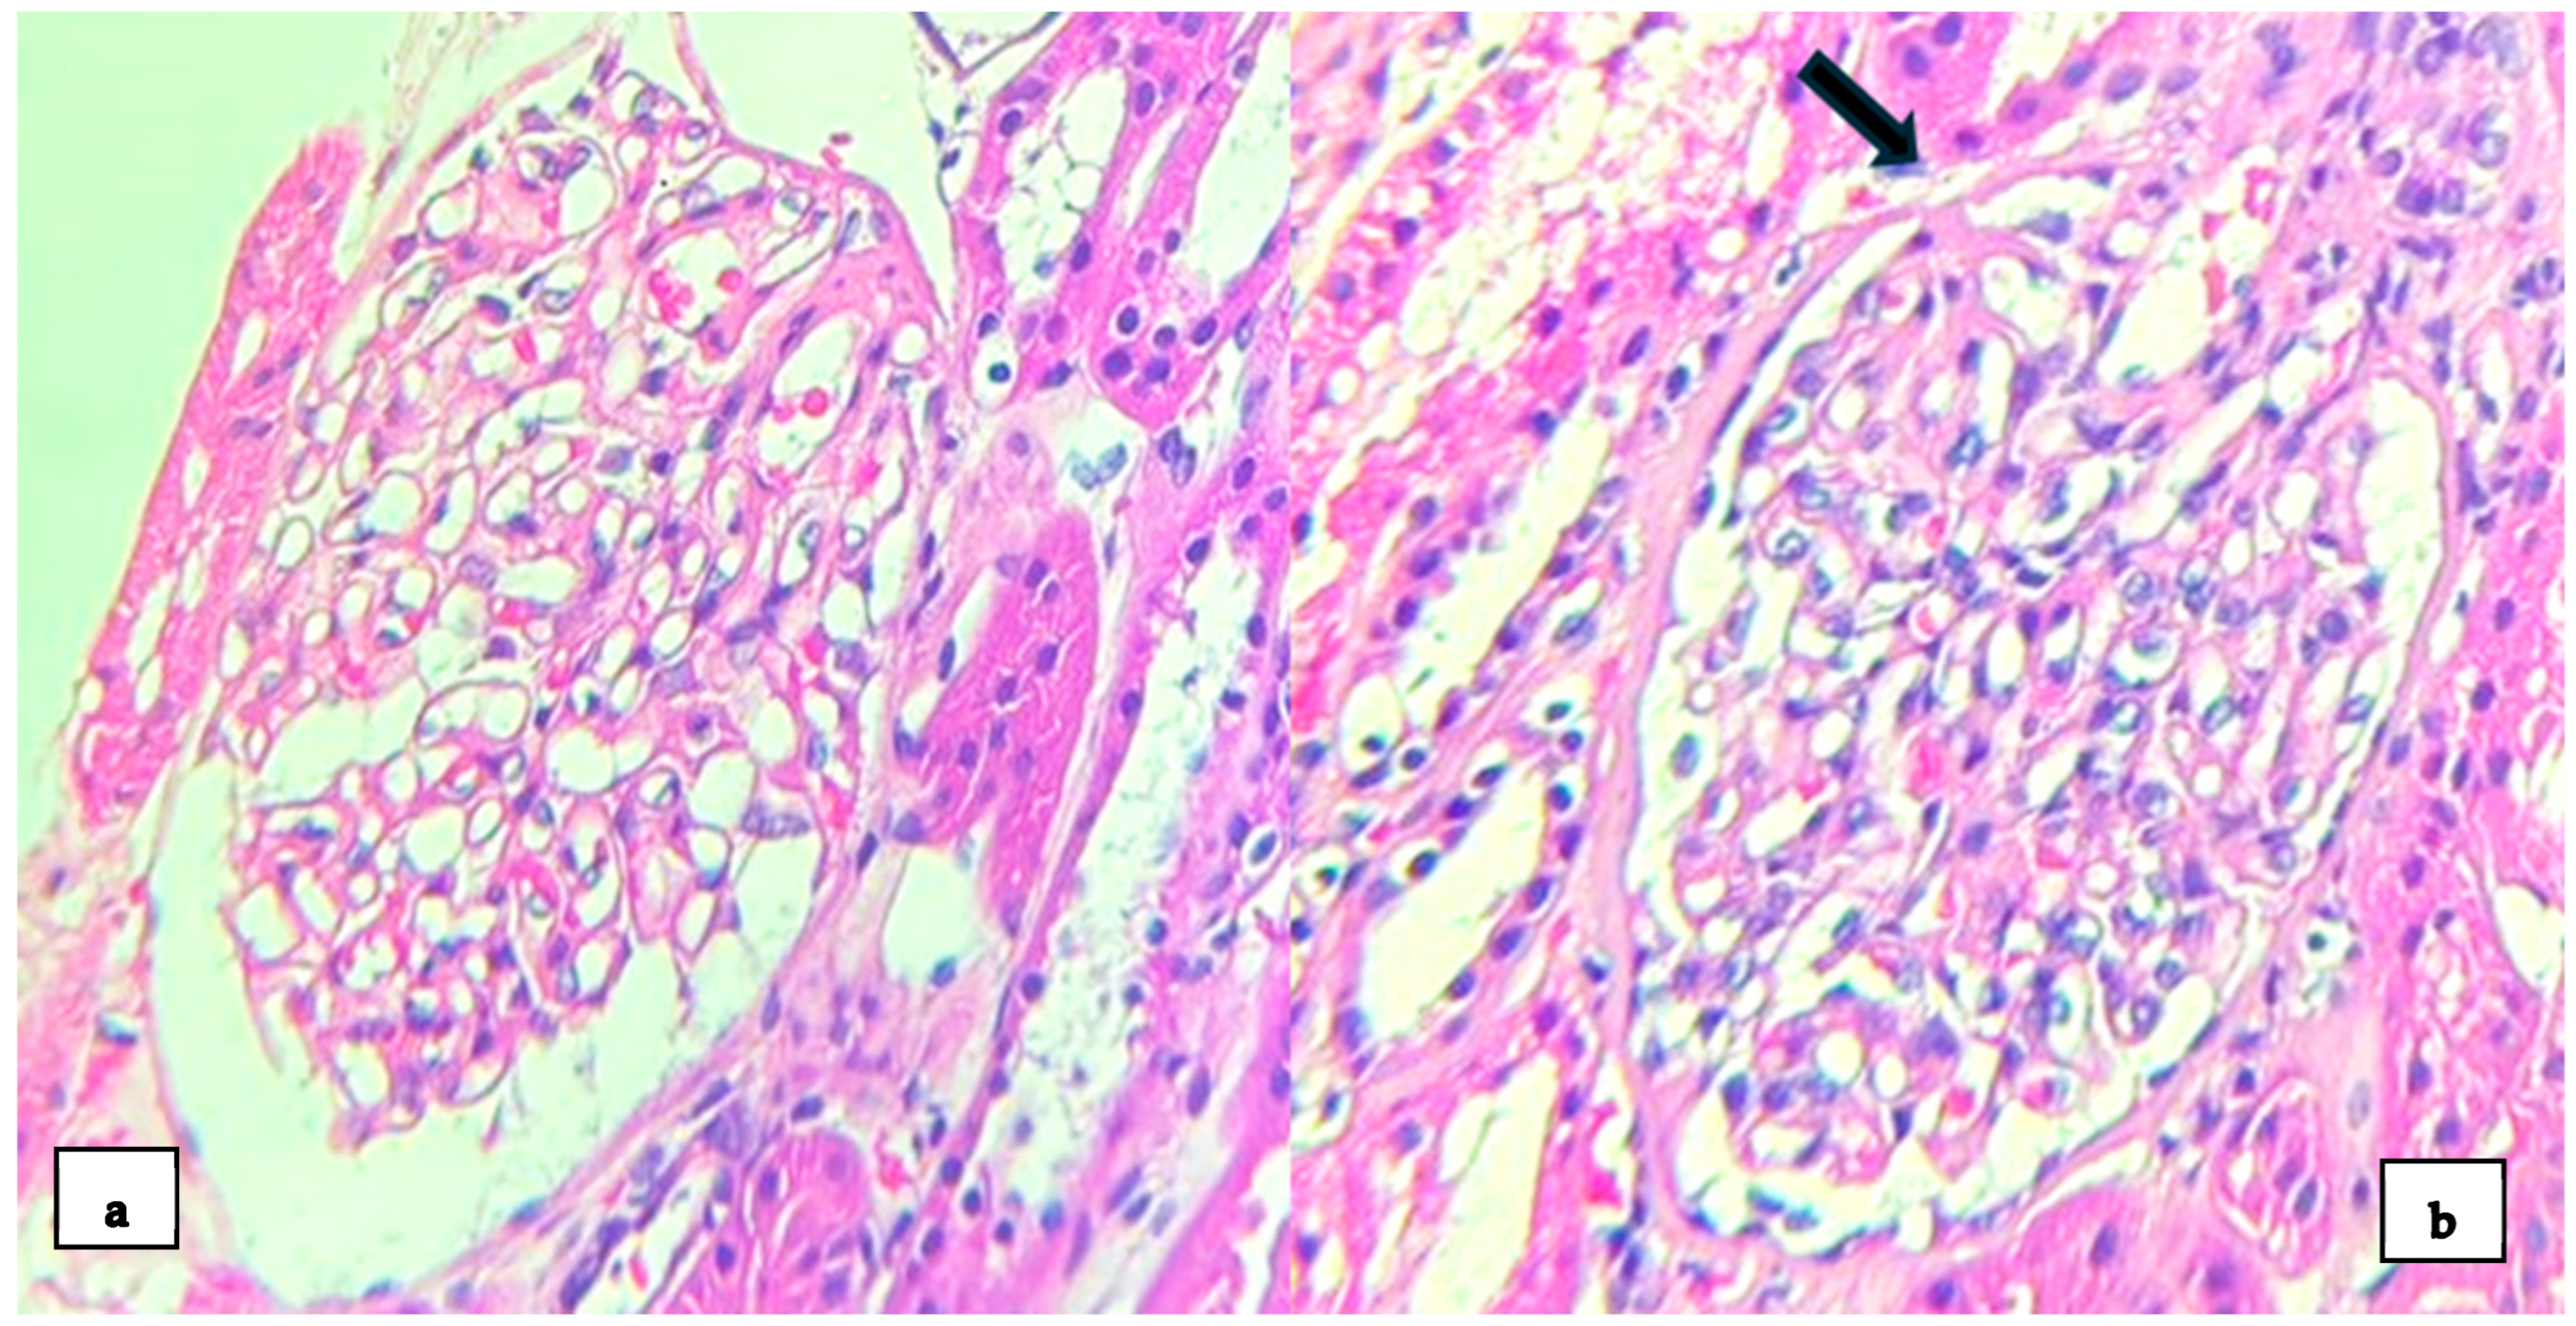

2. Case Presentation